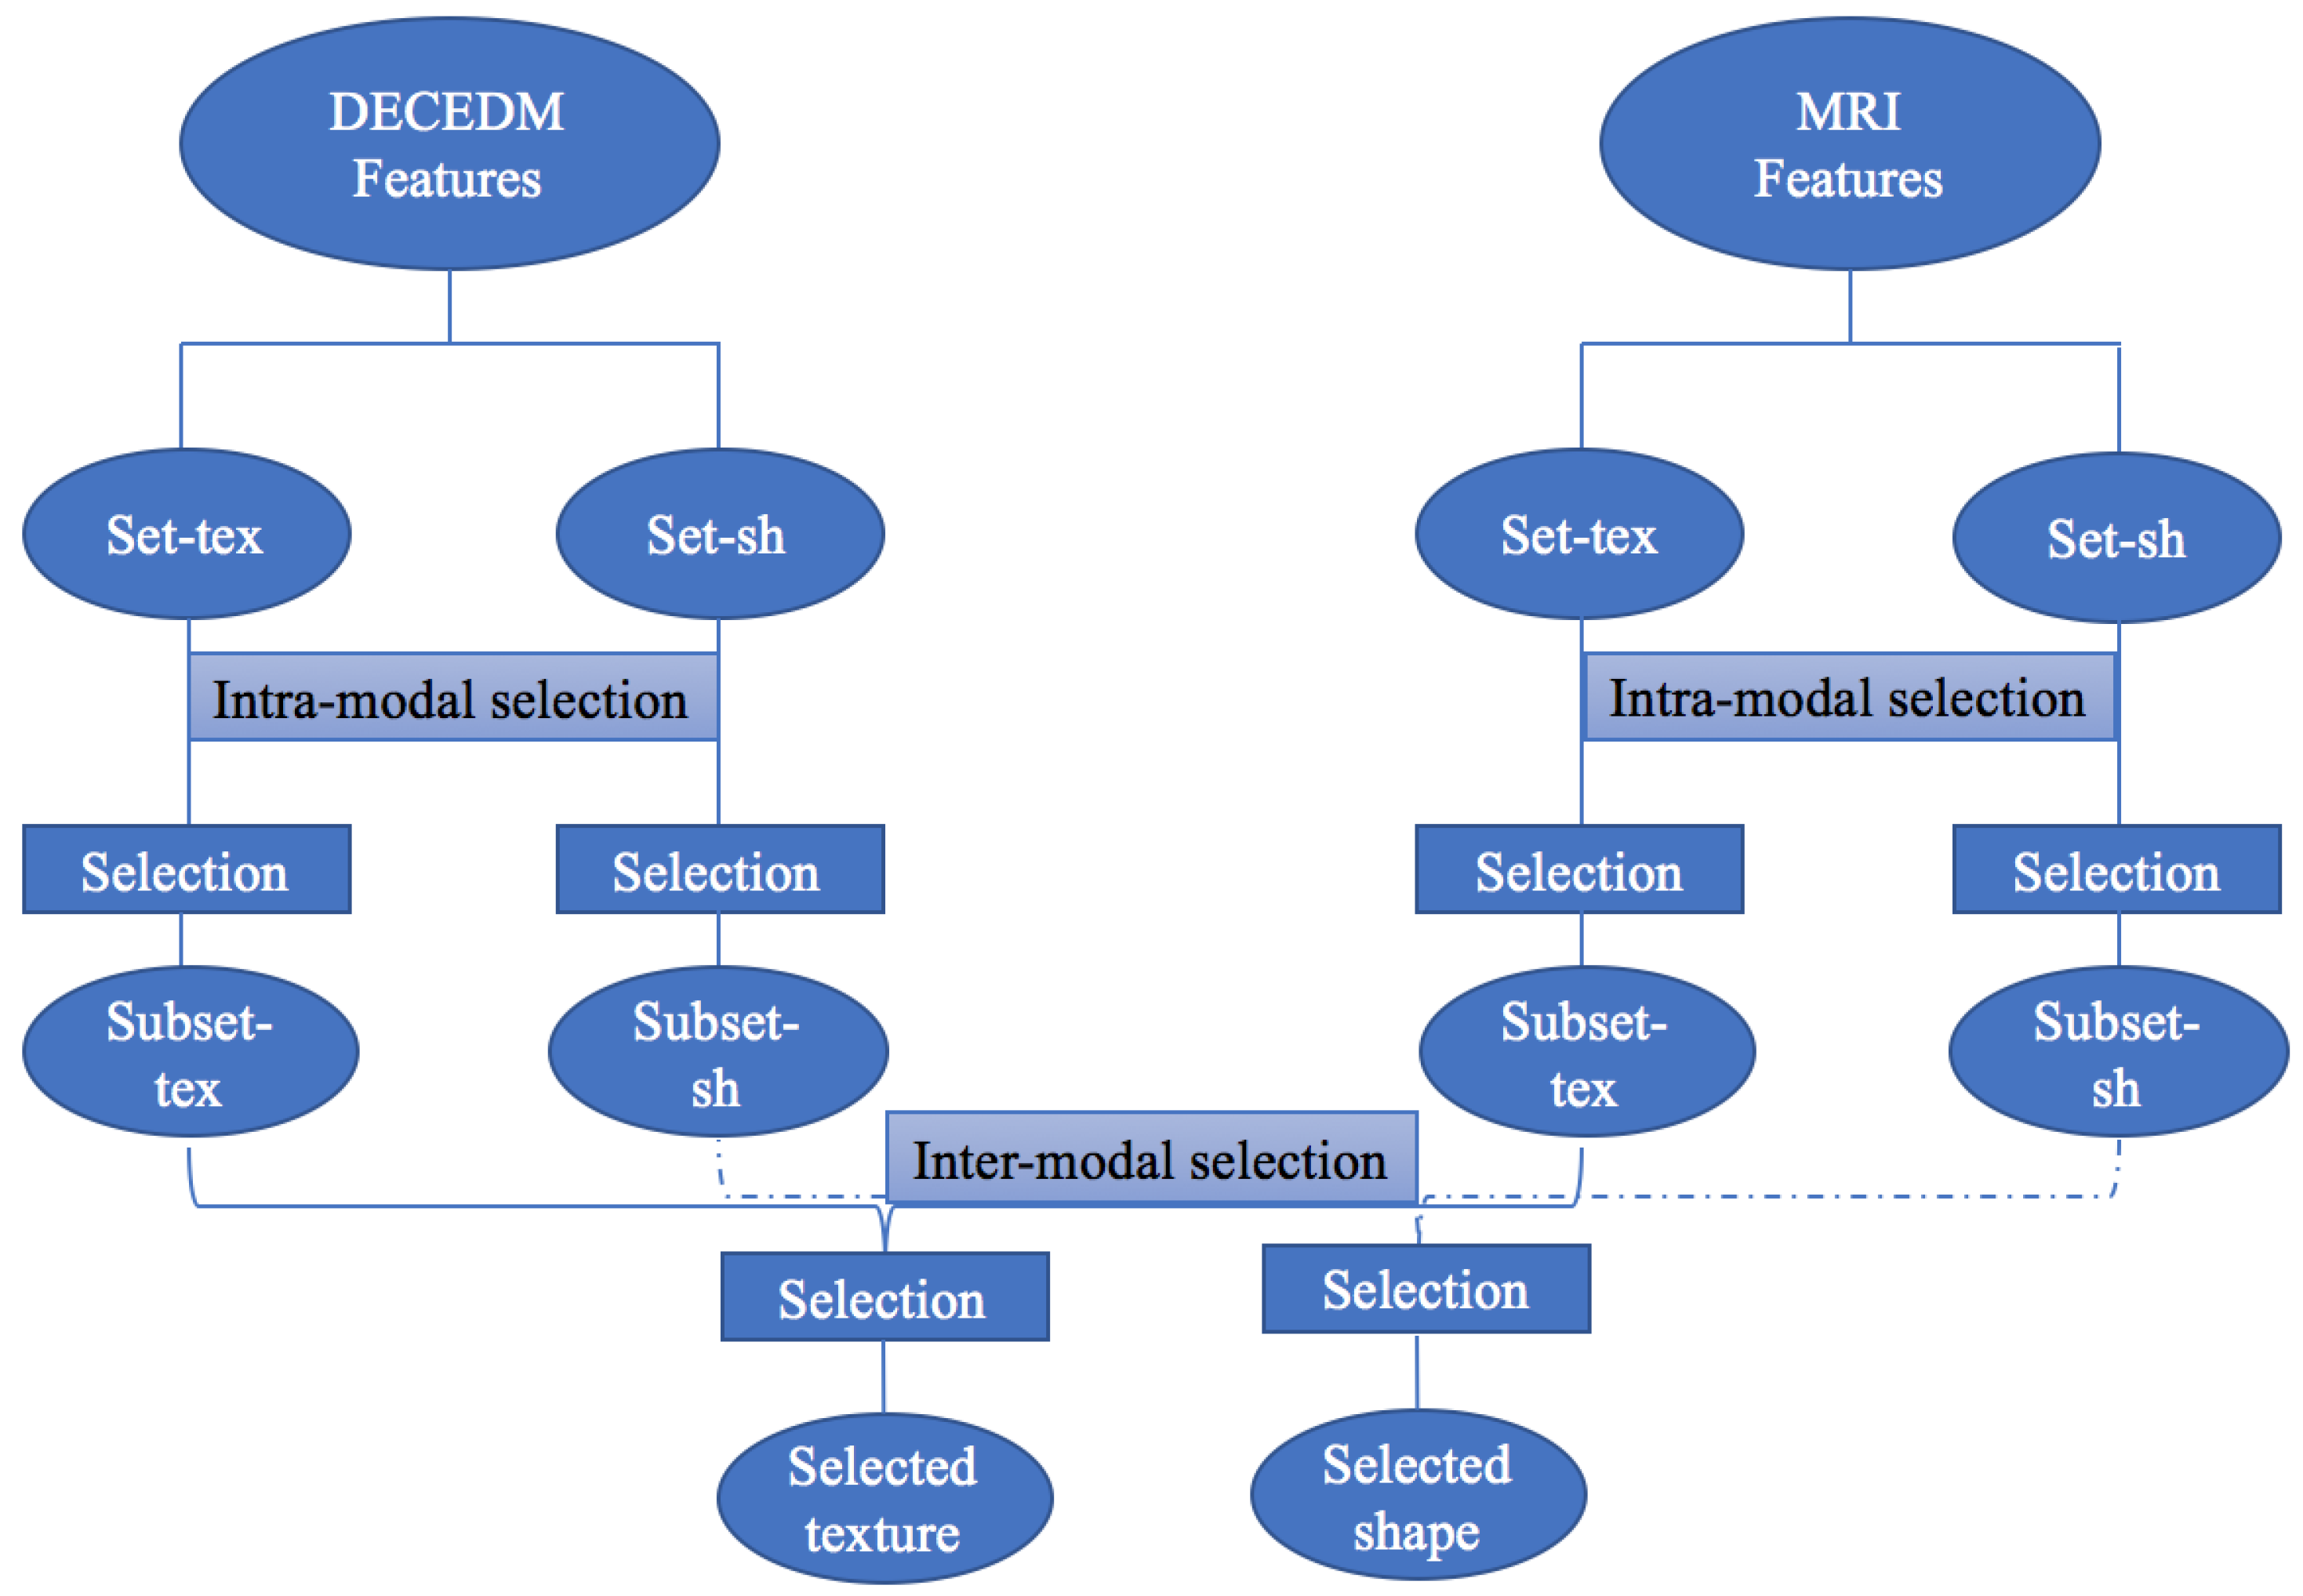

2.4. Bag of Words Modeling

2.5. Image Annotation

3.4. Labeling Results

3.4.1. Performance Metrics

3.4.2. Texture Annotation

3.4.3. Shape Annotation